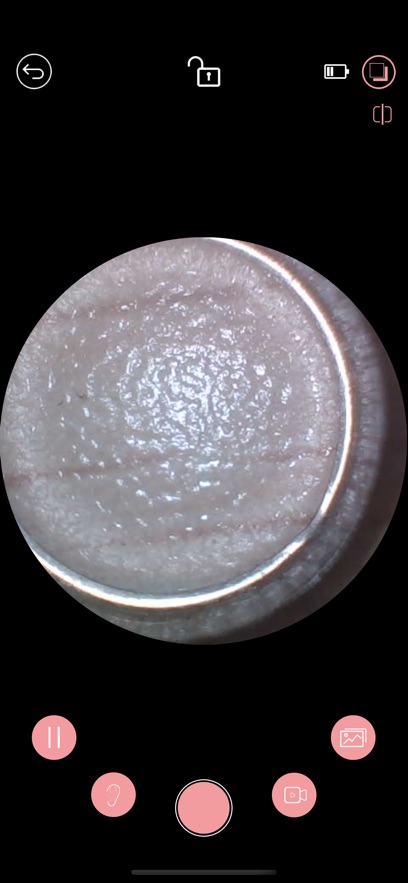

iTiMO耳镜app是一款专业的耳部健康管理应用,通过先进的图像采集技术为用户提供便捷的耳部检查服务。这款应用不仅能够实现可视化的耳部操作,还能帮助用户更安全、更科学地进行耳朵清洁护理。其人性化的设计理念和强大的功能配置,能够满足不同用户的多样化需求,无论是日常护理还是专业检查都能轻松应对。想要体验这款创新医疗科技的朋友,现在就可以下载使用了!

iTiMO耳镜app是一款专为个人及专业医疗场景设计的智能软件,它通过WiFi技术无缝连接各类医疗设备如耳镜、牙镜等,为用户提供高清实时的影像服务。用户只需使用智能手机或平板电脑,就能随时随地查看设备采集的图像,并进行专业的记录与分析。这款软件不仅大幅提升了医疗检查的便捷性和准确性,更为医患沟通搭建了直观高效的互动平台。借助这种创新科技手段,医疗工作者能够更精准地掌握患者病情,同时也能与患者共享检查结果,共同制定最佳治疗方案。